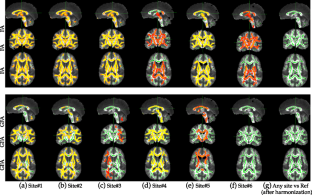

Fig. 1

Fig. 2

Fig. 3

Fig. 4

Fig. 5